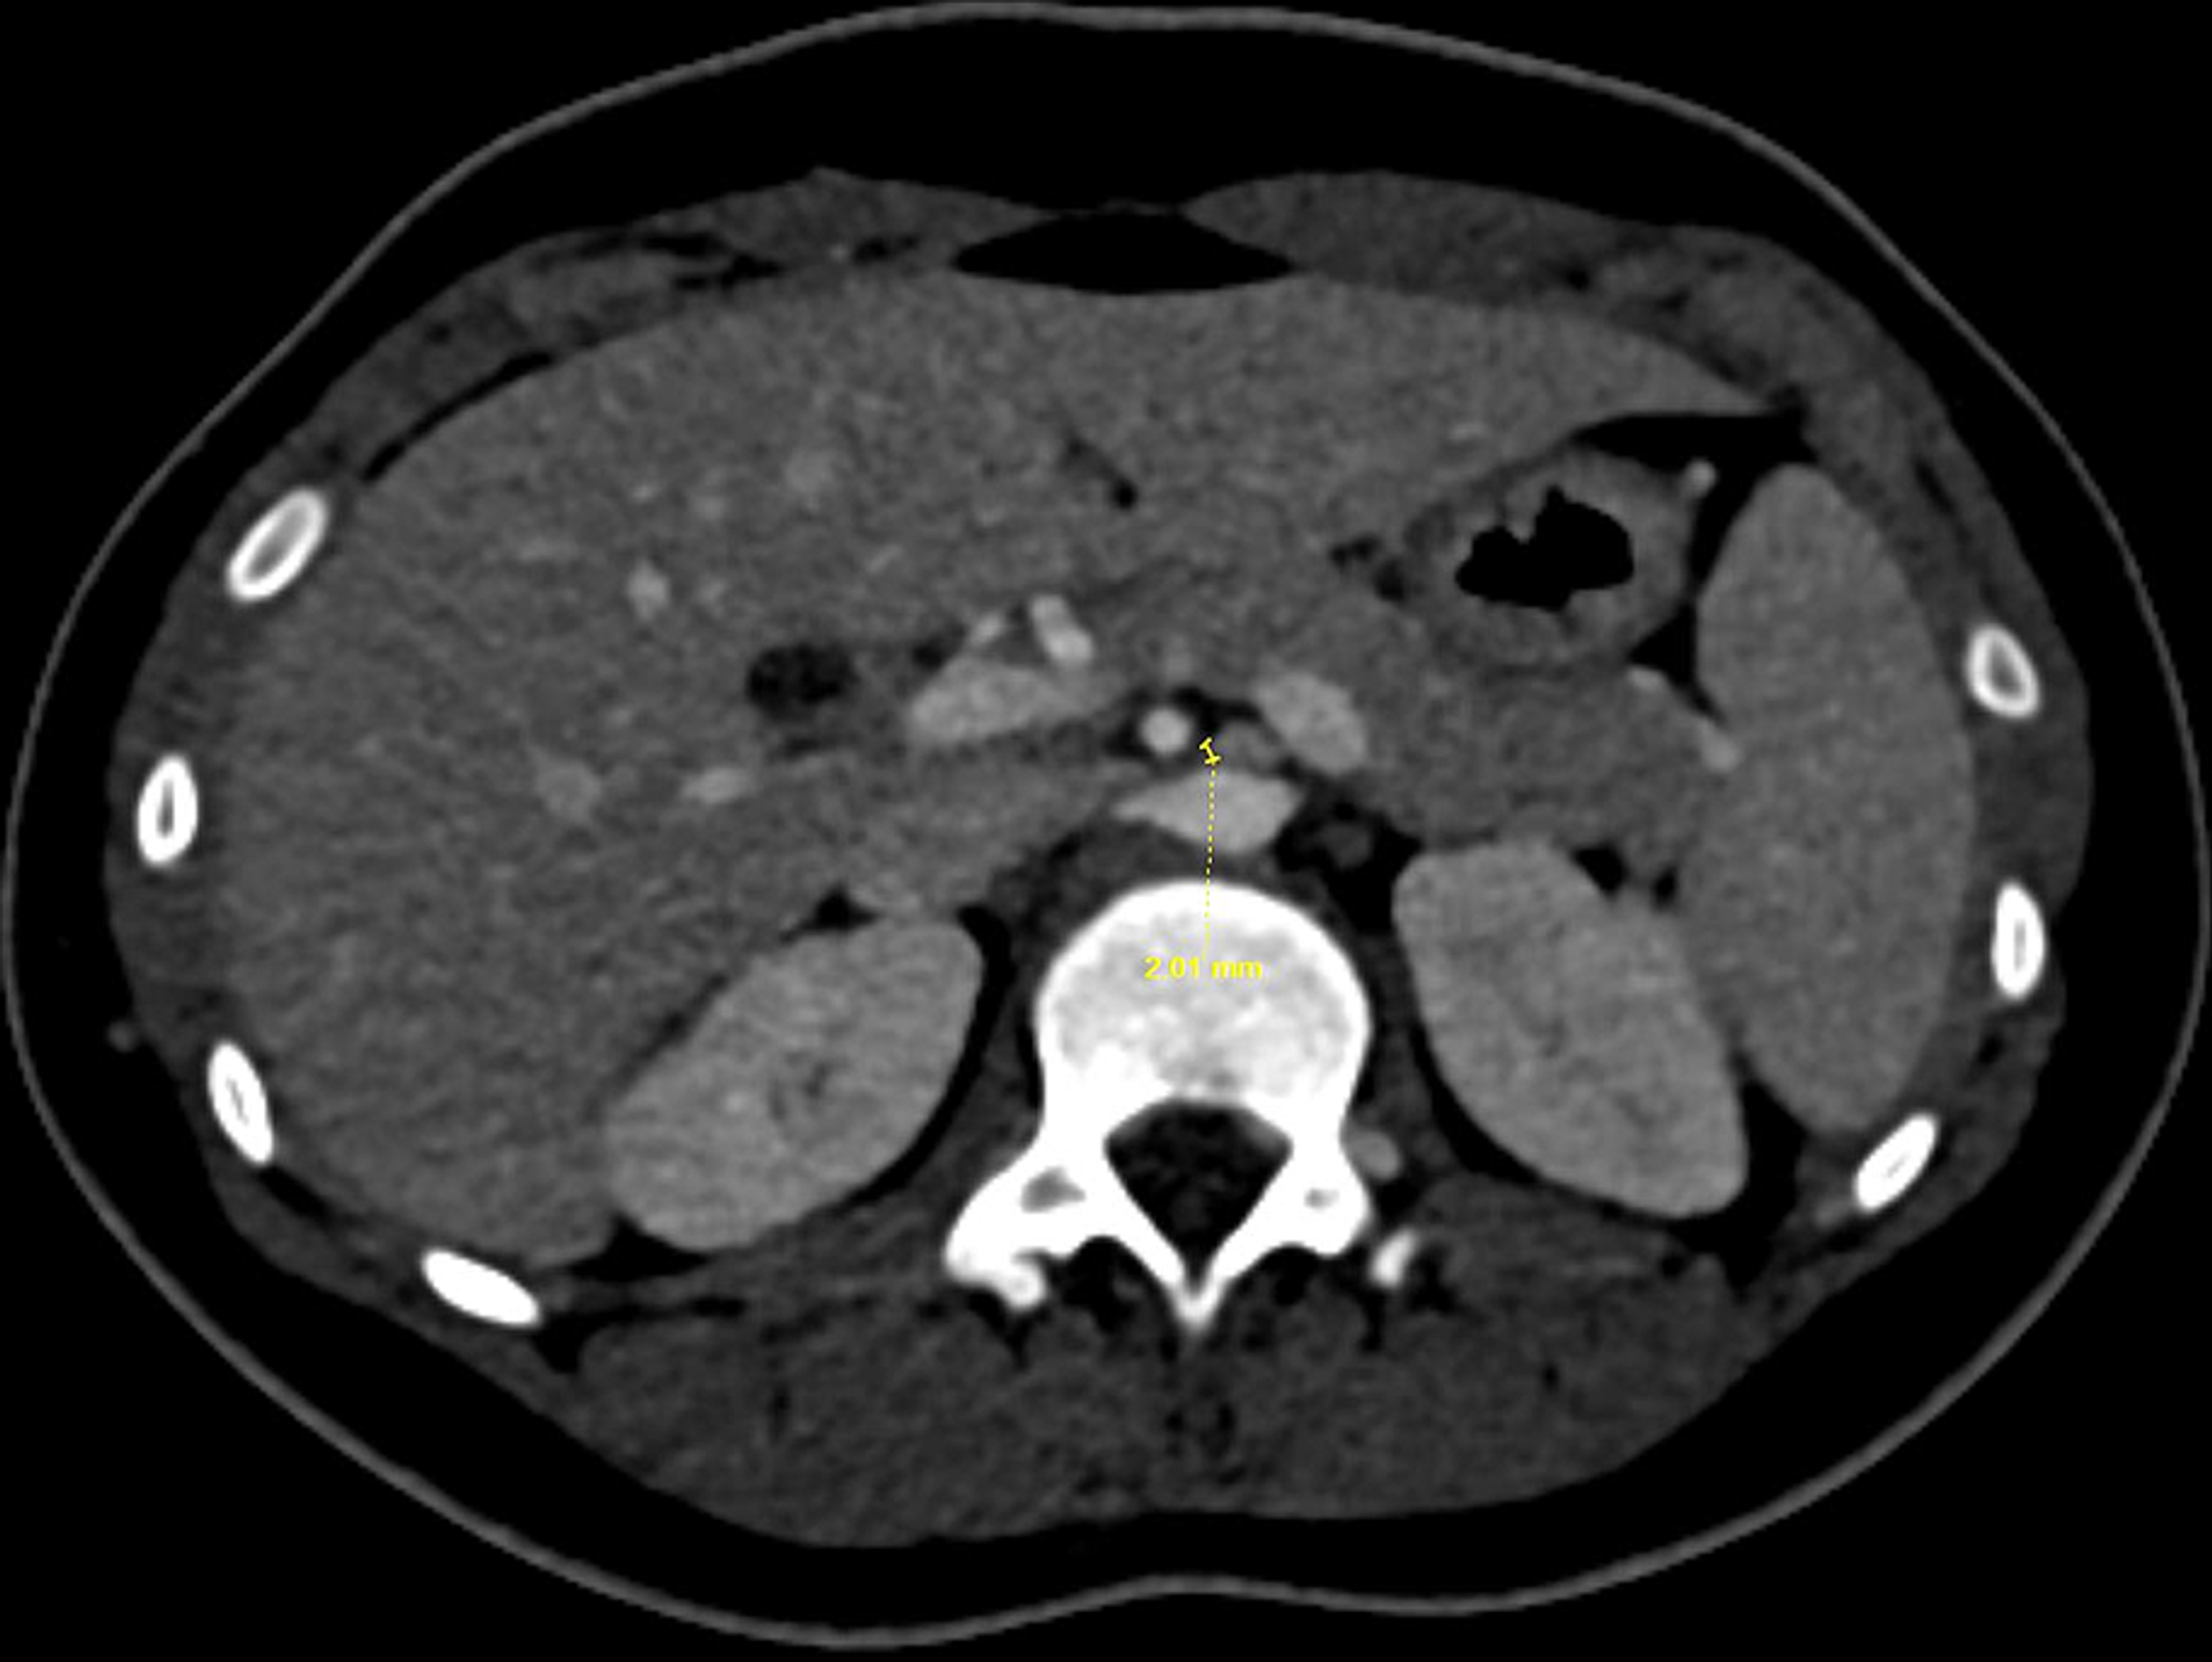

Figure 2 from A Rare Cause of Abdominal and Flank Pain in Children

Figure 1 from Nutcracker SyndromeAn Unusual Case of Chronic Left Upper Nutcracker Syndrome Flank Pain left renal vein (lrv) compression resulting in signs and symptoms is commonly known as nutcracker syndrome. the most common clinical manifestations of nutcracker syndrome are left flank pain, pelvic pain, hematuria, and. nutcracker syndrome (ns) is a condition in which the left renal vein becomes compressed. the nutcracker phenomenon (ncp) is an uncommon condition and refers. Nutcracker Syndrome Flank Pain.

CT Angiography of Posterior Nutcracker Syndrome Radiology Nutcracker Syndrome Flank Pain the nutcracker phenomenon (ncp) is an uncommon condition and refers to the compression of the left renal vein. nutcracker syndrome is the clinical manifestation of the nutcracker phenomenon. The increased left renal vein. nutcracker syndrome (ncs) is an extrinsic compression of the left renal vein (lrv) by the superior mesenteric. nutcracker syndrome (ns) is a condition. Nutcracker Syndrome Flank Pain.